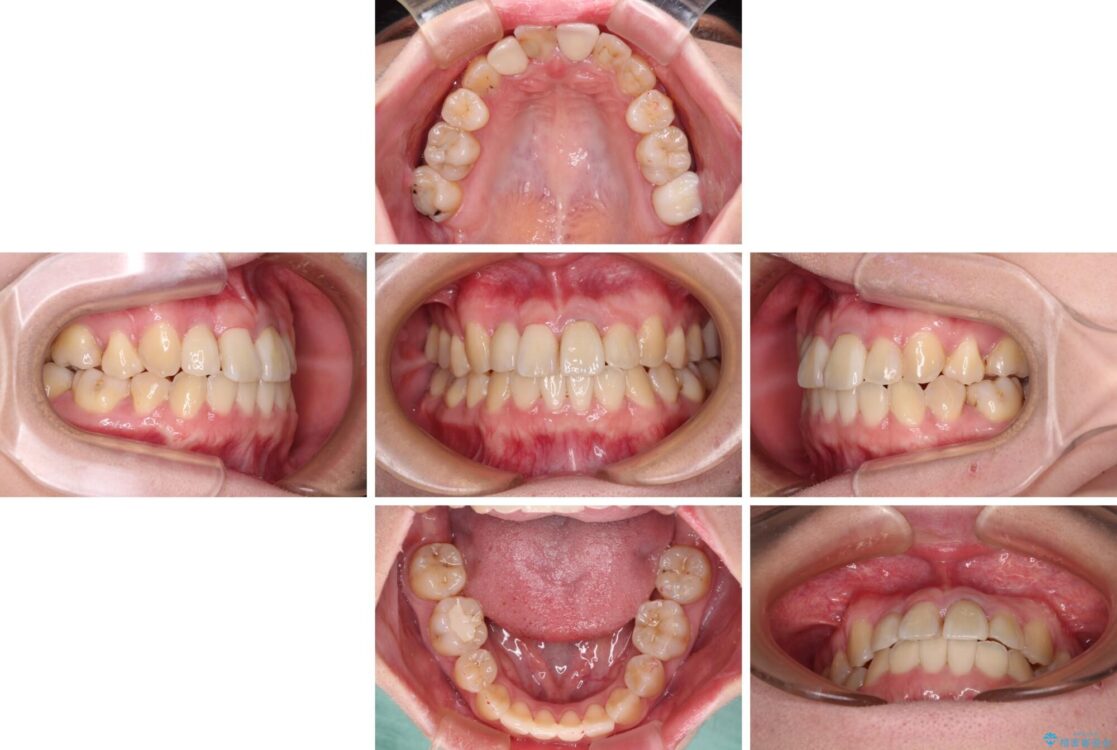

治療前

• 虫歯治療ついでに歯並びの後戻りを改善 インビザラインによる矯正治療 治療前画像